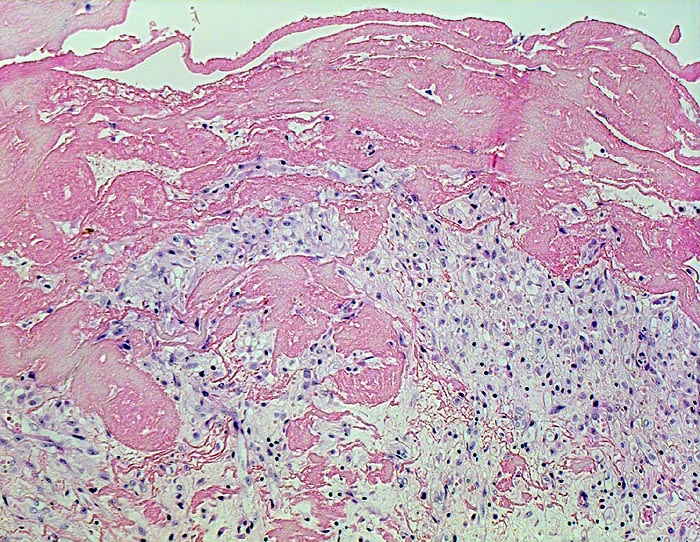

PathoPic – image database / PathoPic ID 4534 - fibrinöse Perikarditis

fibrinöse Perikarditis

Entzündung / Reparatur

Perikard

Körperhöhlen, Serosa

Beschreibung

Klinik

Patientin verstorben in Urämie.

Histologie

100